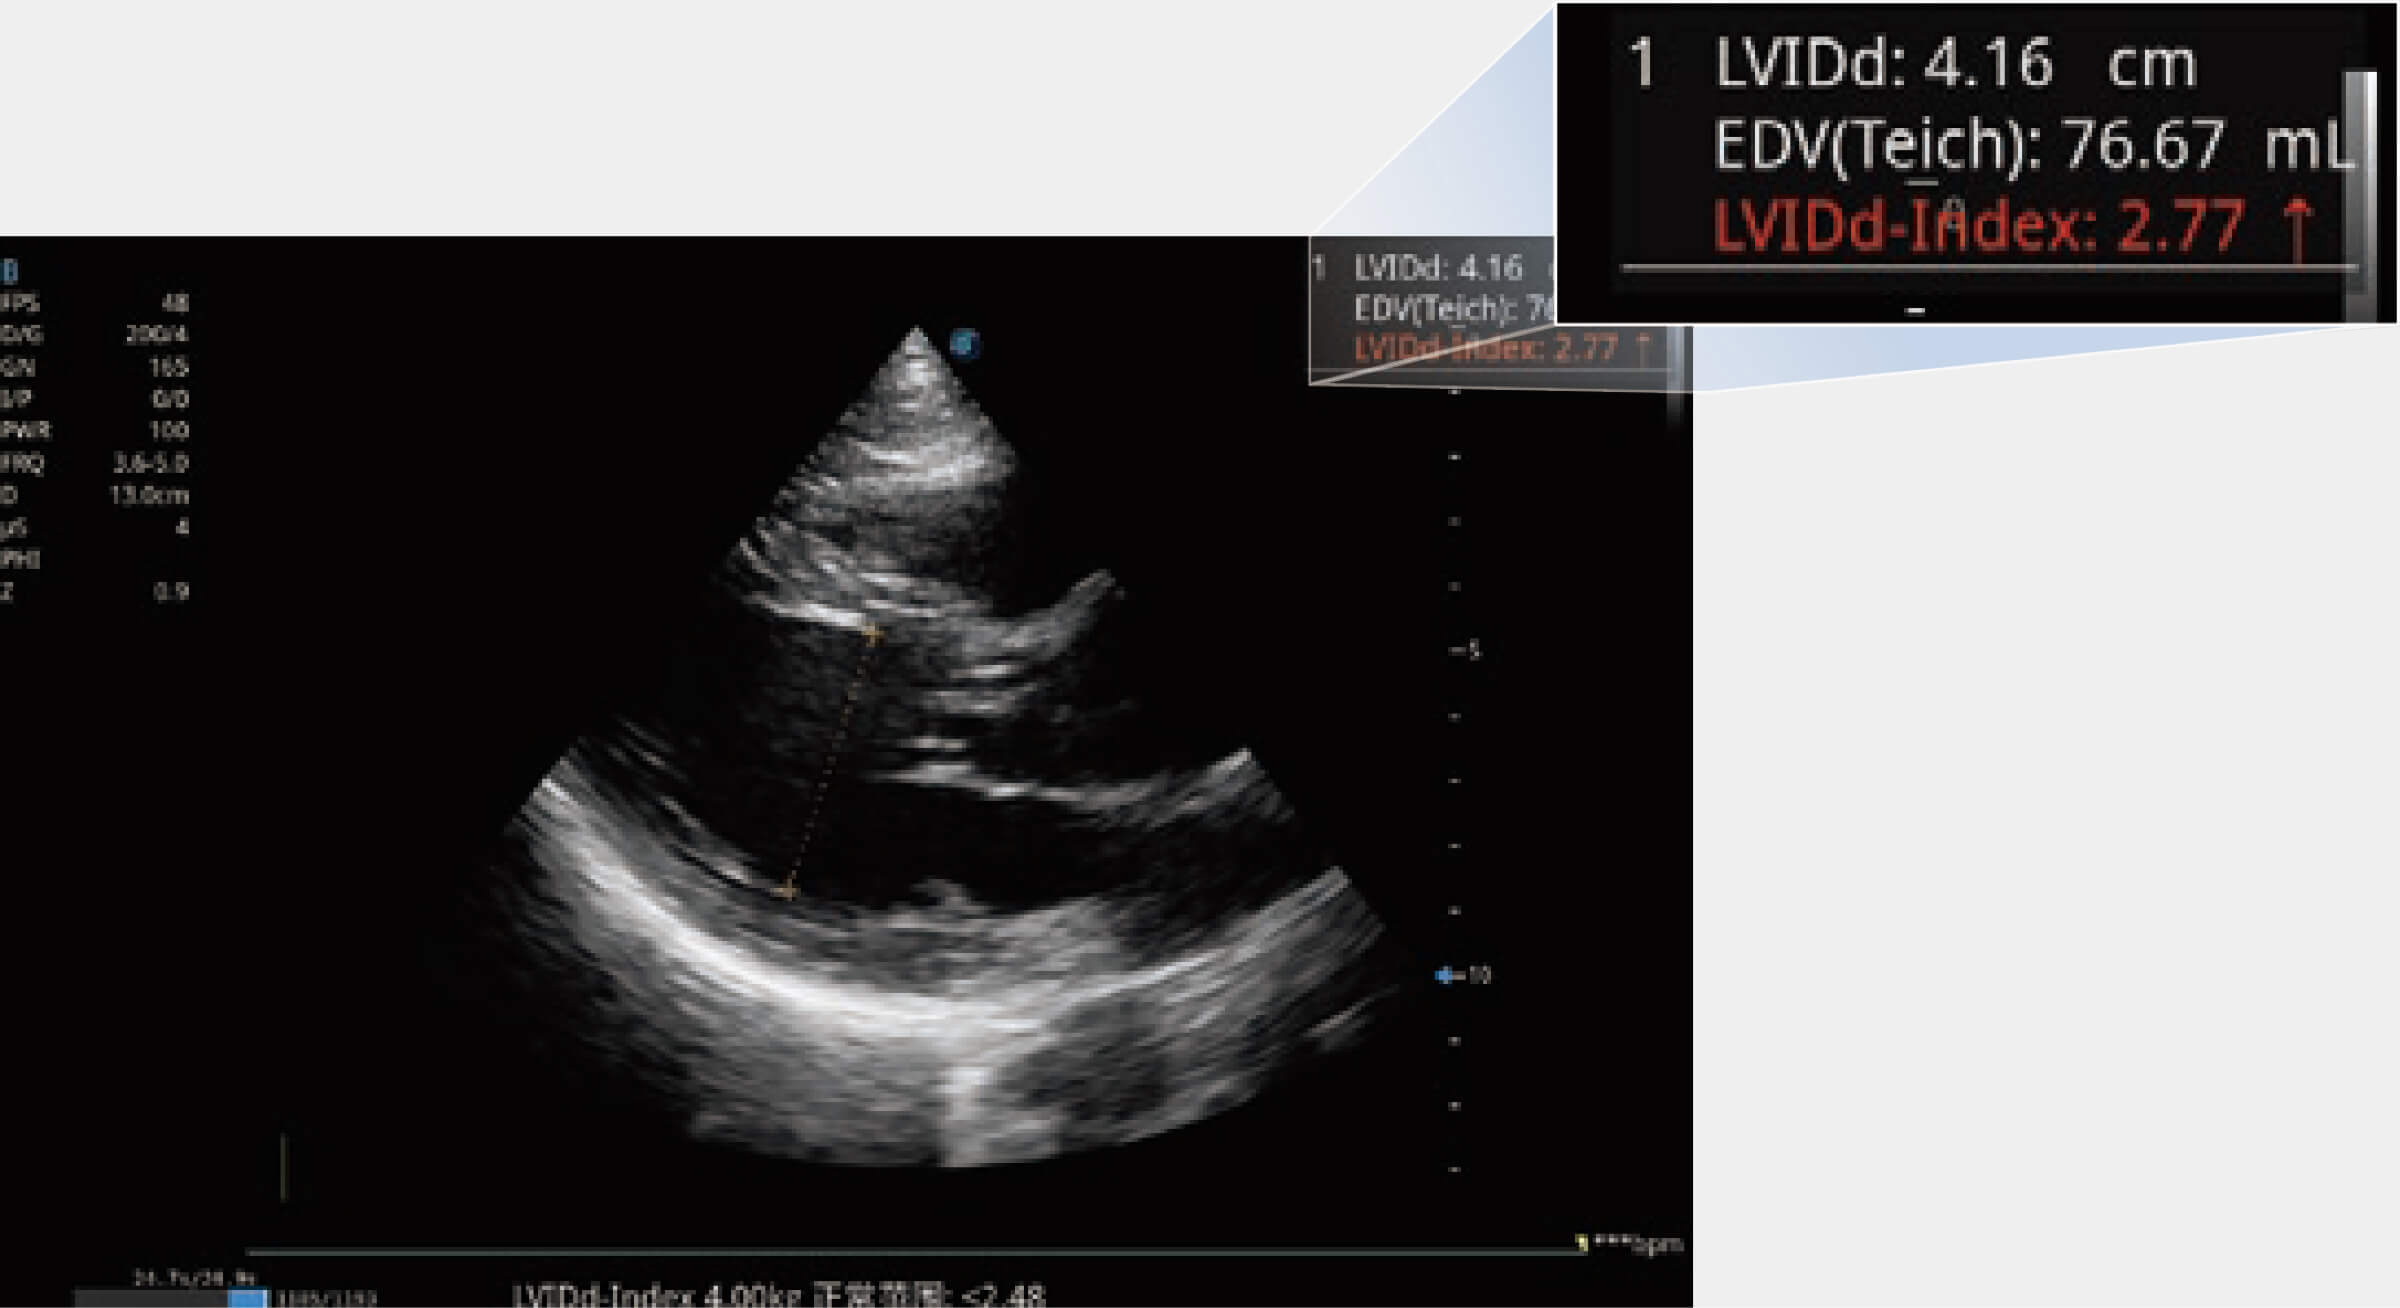

當(dāng)心臟測量結(jié)果超出正常范圍時(shí),可實(shí)時(shí)預(yù)警提示動(dòng)物醫(yī)生,減少疾病漏診概率。